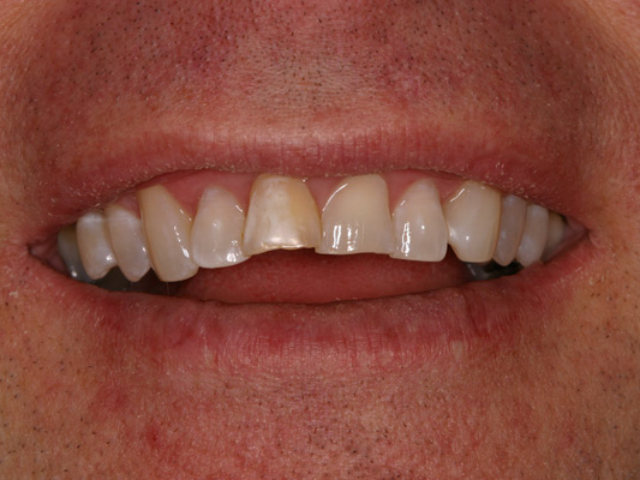

Case Study 14

Problem: This young man was hit by a car while riding his bike. He had multiple fractures in his jaw and three front teeth were fractured.

Plan: Our plan… his fractures were fixed. The trauma left a bony defect which was grafted as well as soft tissue VIP grafts. Placed three separate implants with guided surgery. Molded the tissue and placed Zirconium abutments with porcelain crowns.

A great young man with a confident smile.